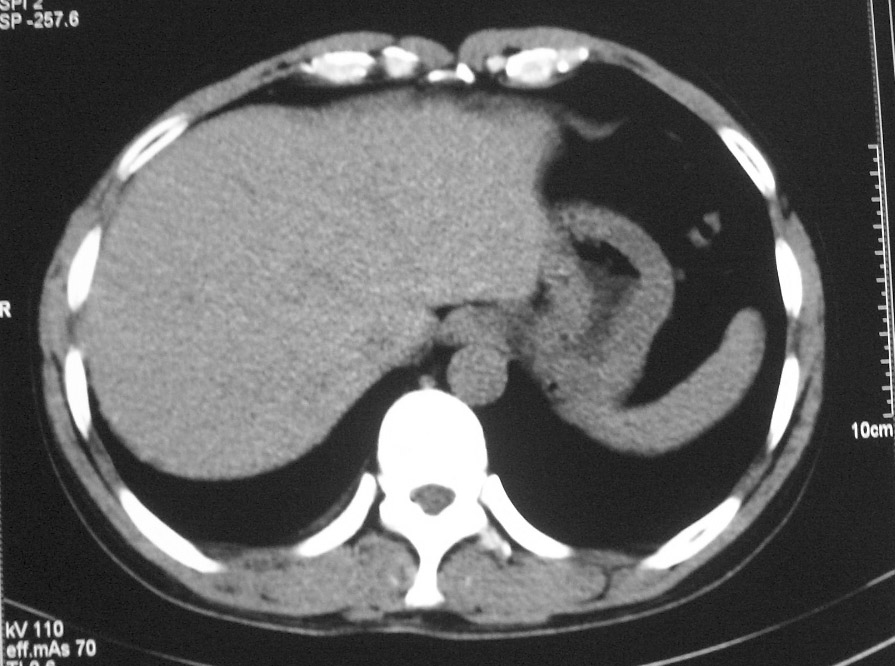

标题: CT5485:[原创]肺部占位请讨论

右上肺ca并肺不张,纵隔淋巴结转移

右肺上叶中央型肺癌并上叶肺不张、纵隔淋巴结肿大

右上叶支气管后壁明显增厚,支持右肺上叶中央型肺癌伴右上叶肺不张、纵隔淋巴结肿大。

右上肺中央性肺癌伴右侧胸腔少量积液!右上肺胸膜下还有一小病灶,不完全排除结核,但个人支持恶性肿瘤!建议早穿刺活检。

右上叶支气管开口变窄,纵隔见肿大的淋巴结。支持右上叶中心型肺癌并右上叶不张纵隔淋巴结肿大。

右肺上叶中央型肺癌并上叶肺不张、纵隔淋巴结肿大.右侧少量胸腔积液。

右肺上叶支气管后壁增厚,呈鼠尾状狭窄,纵隔内未见明显增大的淋巴结影,考虑为中央型肺癌伴右上肺不张